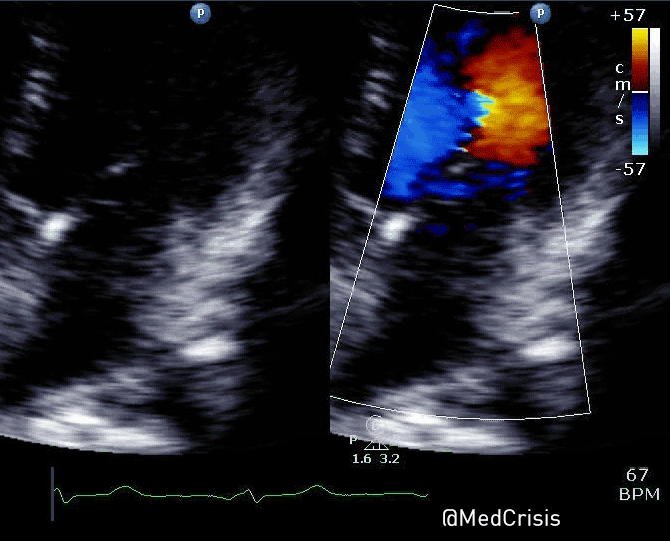

This parasternal short axis view gives the clearest demonstration of the problem. A regional wall motion abnormality is clearly seen affected the infero-septum and inferior wall. The rest of the left ventricle is contracting well.

Therefore one can appreciate why mitral valve problems are more common following an inferior STEMI. In this case an almost akinetic segment, which included the posteromedial papillary muscle, caused the posterior mitral valve leaflet to become fixed, causing mitral regurgitation. Even though overall left ventricular function was only mildly impaired on the echocardiogram, the regurgitant pressure into the lungs can precipitate pulmonary oedema.